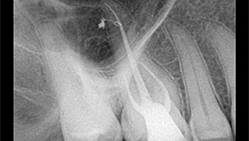

Slika 3: Nekrotičan/zaražen zub: donji premolar pacijenta koji se žali na konstantan, pulsirajući bol. Infekcija nije ograničena samo na apikalni deo već je takođe locirana i u srednjem delu lateralnog kanala. Postoperativni rendgenski snimak pokazuje 3-D zaptivanje apikalne regije sa svim anastomozama lateralnog i pomoćnih kanala.